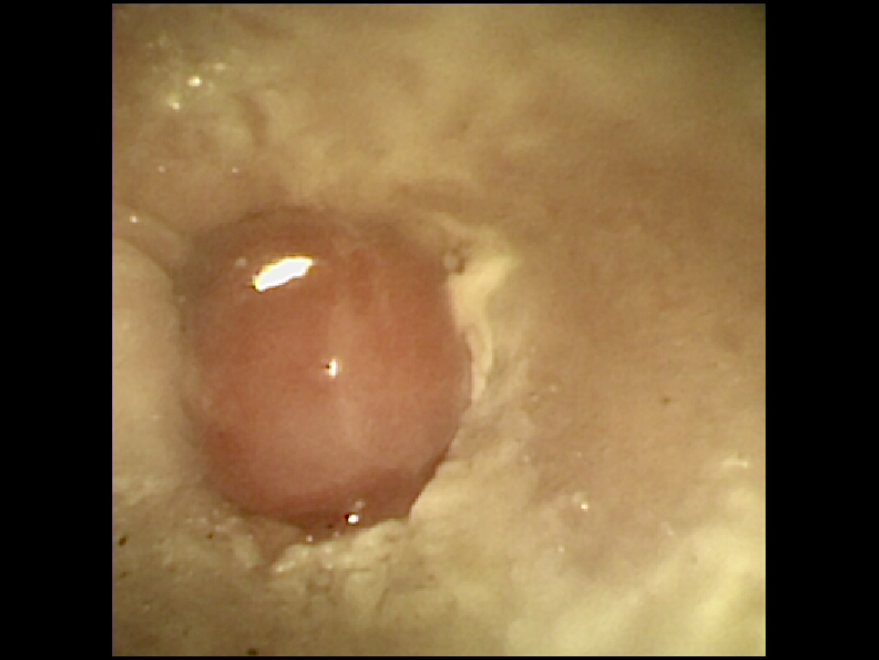

고양이 외이염의 원인이 되고 있는 이도 내 신생물을 확인할 수 있었습니다.

이러한 고양이 이도 내 신생물, 고양이 외이도 내 폴립은 대부분의 경우 양성이지만, 이로 인해 지속적인 외이염 및 염증성 삼출의 원인이 되기 때문에 제거가 필요 합니다.

크기가 너무 크거나, 주변조직에 침습 되어 있는 경우에는 외이도적출 또는 전이도적출이 필요할 수 있지만,

작은 크기와 침습이 없는 폴립의 경우 내시경을 통해 제거할 수 있습니다.